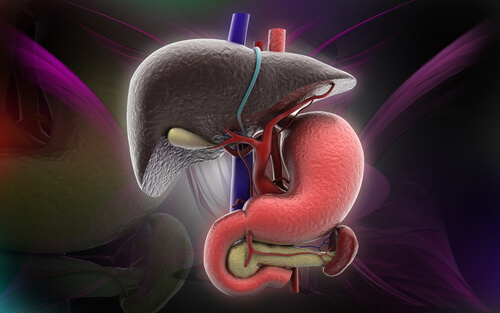

El nombre científico del hígado graso es esteatosis hepática y generalmente se asocia con la obesidad y el colesterol alto, pero también se puede presentar por un consumo excesivo de alcohol o por un síndrome metabólico como la diabetes y la hipertensión.

Es bastante difícil detectarla, pero existen algunos síntomas que pueden dar indicios de esta enfermedad que se genera cuando la grasa se acumula en las células hepáticas. En muchos casos estas células adiposas se llenan de grasa y “pasan” el exceso a los órganos cercanos.

Es importante saber que el hígado cumple funciones vitales para el organismo, produce proteínas, regula el metabolismo de la grasas, elimina las toxinas de la sangre y controla la cantidad de aminoácidos a nivel general, por lo que es fundamental mantenerlos en perfecto estado.

Se presenta una “puntada” o incomodidad en el centro o parte superior derecha del abdomen. No tiene que ver con una actividad ni esfuerzo puntual. Puede aparecer luego de comer, ya que el estómago se expande y presiona sobre el hígado agrandado.

El hígado graso es la presencia de líquidos entre los peritoneos visceral y parietal, y deriva de una enfermedad hepática, por lo que los síntomas son distensión abdominal, indigestión, dolor en la espalda baja y dificultad para respirar. También pueden presentarse edemas en los tobillos.